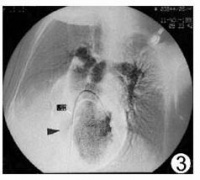

三尖瓣下移畸形是一种罕见的先天性心脏畸形。1866年Ebstein首先报道一例,故亦称为Ebstein畸形。其发病率在先天性心脏病中占0.5~1%。三尖瓣下移畸形系指三尖瓣畸形,其后瓣及隔瓣位置低于正常,不在房室环水平而下移至右心室壁近心尖处,其前瓣位置正常,致使右心房较正常大,而右心室较正常小,可有三尖瓣关闭不全。此类畸形常合并卵圆孔开放或房间隔缺损以及肺动脉狭窄。由于右心房内血量较多,压力增高,其所含血液部分经房间隔缺损或卵圆孔流入左心房,部分仍经三尖瓣入右心室,因肺动脉狭窄,进入肺循环的血量减少,故回入左心房的动脉血量也少,此时再与自右心房分流来的静脉血混合,经二尖瓣而入左心室体循环。详细见三尖瓣下移畸形。